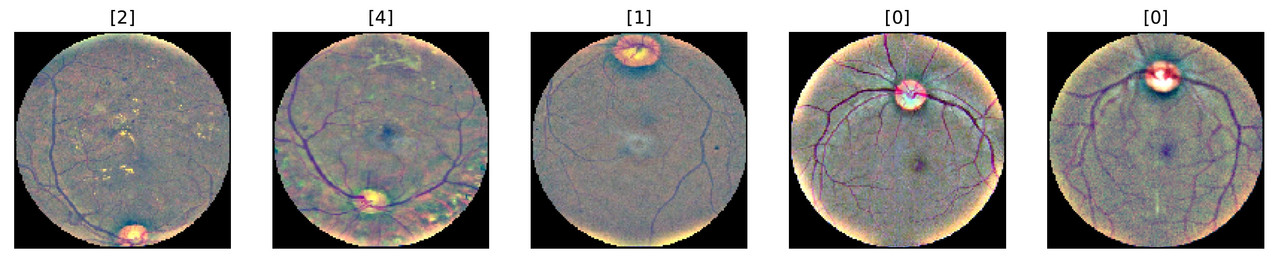

The illustration further emphasizes differences in the aspect ratio and lighting conditions.

The severity of DR is diagnosed by the presence of visual cues such as abnormal blood vessels, hard exudates and so-called cotton wool spots. You can read more about the diagnosing process here. Comparing the sample images, we can see the presence of exudates and cotton wool spots on some of the retina images of sick patients.